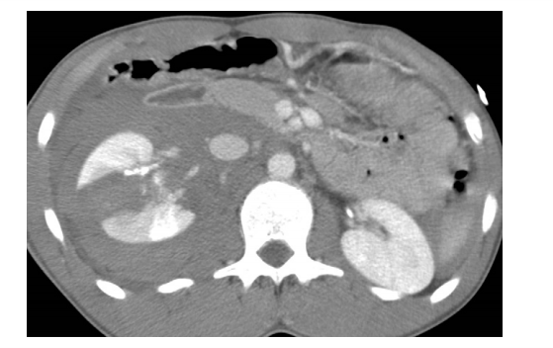

is this mass enhancing?

yes!

new finding. Management?

excise it